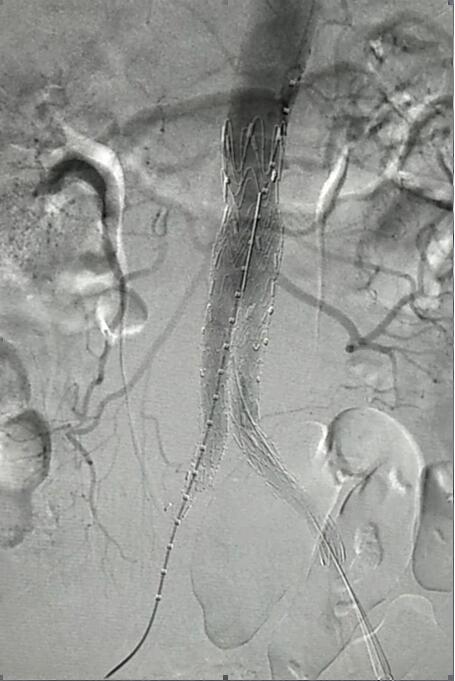

血管介入科行腹主動脈瘤覆膜支架隔絕術(shù)(“褲衩”支架植入)。圖2